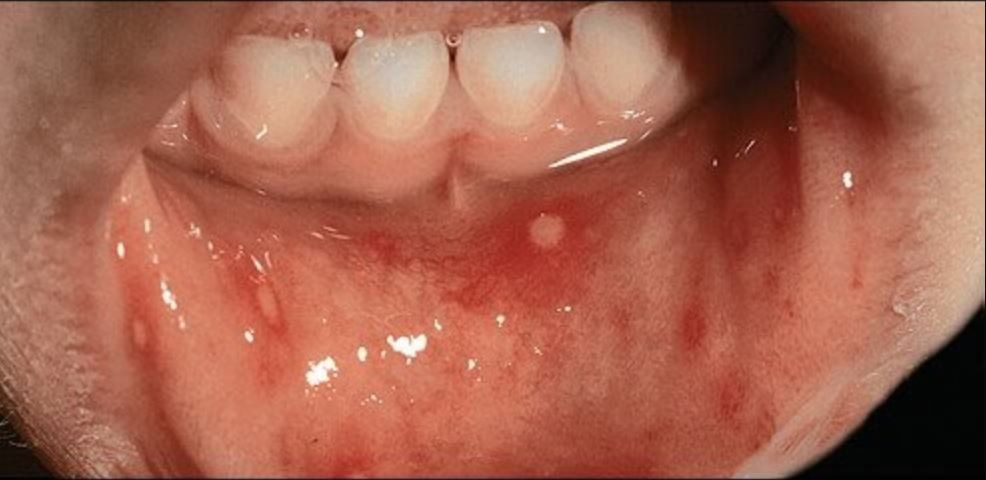

Bệnh tay chân miệng là một bệnh truyền nhiễm phổ biến nhưng khá lành tính, thường gặp ở trẻ nhỏ vào cuối mùa hè và đầu mùa thu. Coxsackievirus A16 và các chủng khác cùng loại là nguyên nhân gây ra bệnh. Các triệu chứng ban đầu bao gồm sốt nhẹ và khó chịu. Sau đó, trên vòm miệng, lưỡi, niêm mạc miệng và lưỡi gà của bệnh nhi sẽ xuất hiện các tổn thương dạng mụn nước, gây đau đớn và khó khăn trong việc ăn uống. Ở trẻ em nhỏ, tình trạng khó nuốt và chảy nước dãi do mụn nước ở miệng có thể dẫn đến mất nước, rất đáng lo ngại. Khoảng 1 - 2 ngày tiếp theo, các tổn thương này sẽ bắt đầu phát triển ở những bộ phận khác của cơ thể. Mụn nước có hình tròn hoặc bầu dục, bao quanh là một vầng hồng ban. Các cạnh của lòng bàn tay và lòng bàn chân là vị trí ưa thích của mụn nước, nhưng tổn thương vẫn có thể xảy ra trên toàn bộ cơ thể.

Nhiều tổn thương mụn nước nhỏ và rời rạc ở ngón tay, lòng bàn tay; tổn thương tương tự cũng xuất hiện trên bàn chân. Một số mụn nước thường dễ nhận thấy đường giới hạn xung quanh rõ ràng.